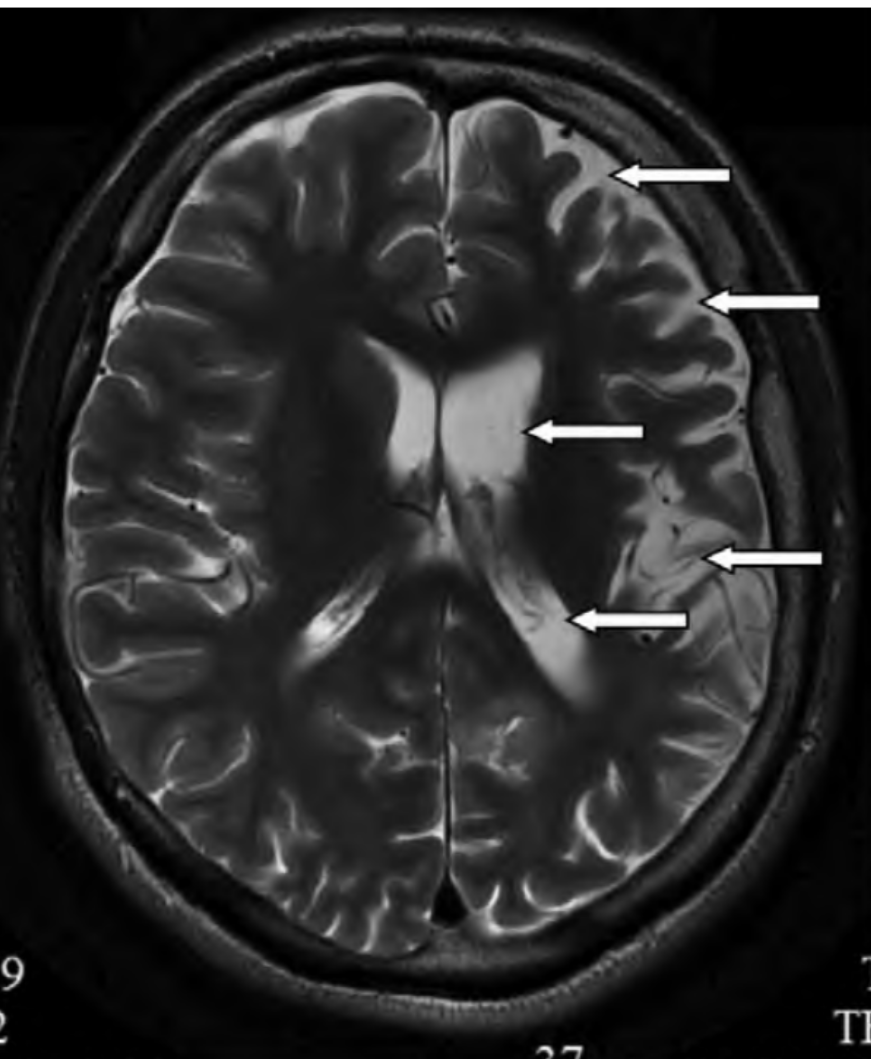

МРТ 7-летнего ребенка с данной формой энцефалита (пример из статьи Ващилина Т.С.): выражена асимметрия боковых желудочков, расширены субарахноидальные пространства